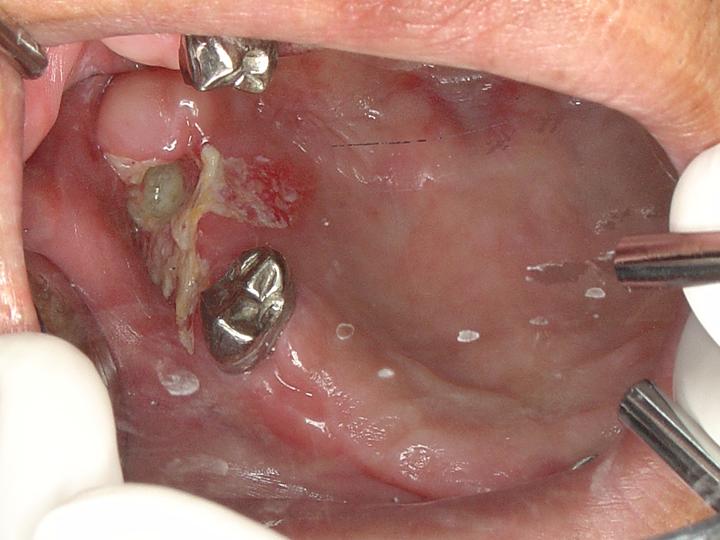

※ [本文轉錄自 medstudent 看板] 作者: simon88 (齒時齒刻) 看板: medstudent 標題: [問題] case conference (about 口腔) 時間: Sat Oct 28 00:51:33 2006 http://oralpathol.dlearn.kmu.edu.tw/dd/2006-D5-CPC-1-data/D5-cpc-1-clinical%20picture.JPG

臨床照片 http://oralpathol.dlearn.kmu.edu.tw/dd/2006-D5-CPC-1-data/D5-cpc-1-XRay.JPG

牙科門診紀錄 請問一下 這有可能是什麼相關疾病? 干蝦! -- ※ 發信站: 批踢踢實業坊(ptt.cc) ◆ From: 220.143.129.147 ※ 編輯: simon88 來自: 220.143.129.147 (10/28 00:54)

paugo:如果病人有做過電療 ORN 10/28 03:03

paugo:不然我的Dx.是 osteomyelitis 10/28 03:07

yuiwei:白色部份 可抹掉...那有可能是砍地達... 10/28 09:51

yuiwei:如果...17 不是拔三年 且周圍白班是不可抹去.. 10/28 10:00

yuiwei:那就要R/O SCC..... 10/28 10:02